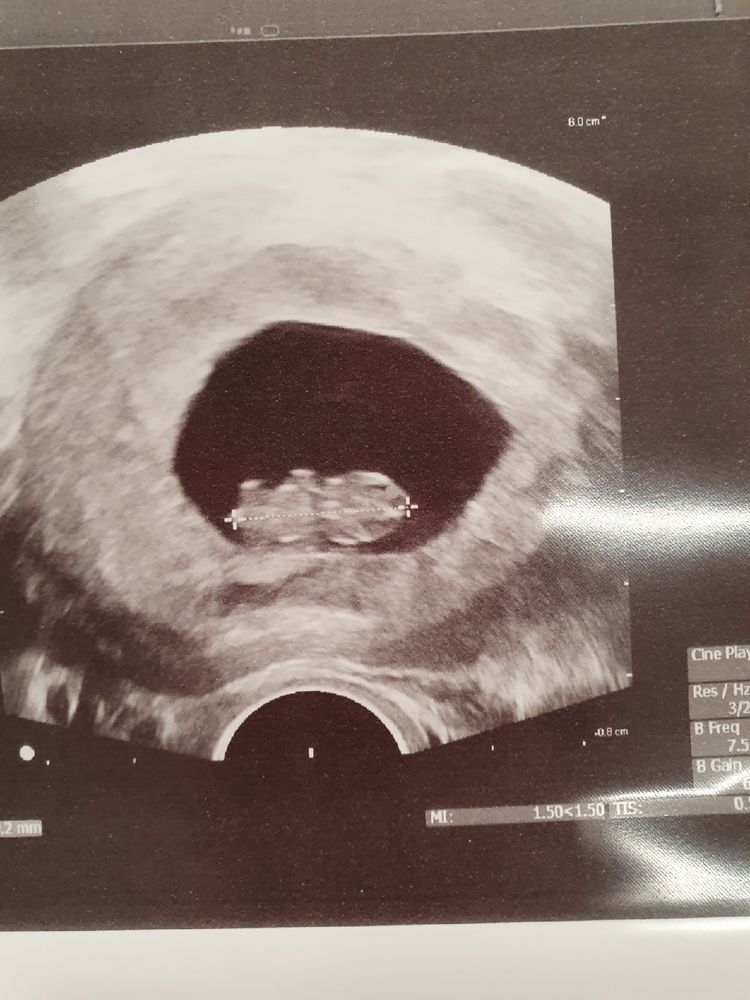

8нед 2 дня

Мы уже такие большие! двигали ручками)

ктр 19мм!

в общем все хорошо, растем! теперь 7 марта поеду становиться на учет)